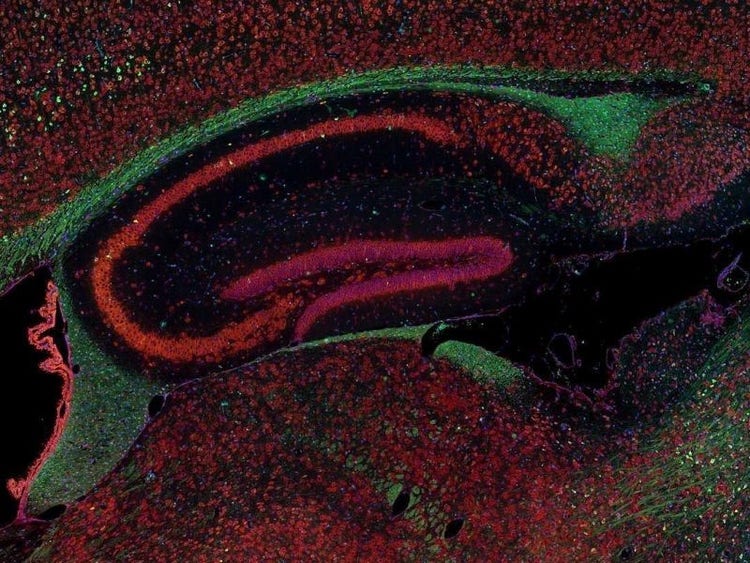

Fluorescence imaging of a mouse brain

Cette vue d’un cerveau de souris est en réalité constituée par l’assemblage d’une multitude d’images prises par imagerie de fluorescence.

Le scientifique britannique Sir George G. Stokes a d’abord constaté que la fluorine minérale devenait fluorescente lorsqu’elle était éclairée par une lumière ultraviolette, et il a inventé le mot « fluorescence ». Stokes a remarqué que la lumière fluorescente présentait des longueurs d’onde supérieures à celles de la lumière d’excitation, un phénomène aujourd’hui connu sous le nom de « déplacement de Stokes ». La microscopie de fluorescence est une excellente méthode pour étudier une matière qui peut devenir fluorescente soit sous sa forme naturelle (appelée fluorescence primaire ou autofluorescence), soit lorsqu’elle est traitée avec des produits chimiques qui peuvent devenir fluorescents (appelée fluorescence secondaire).